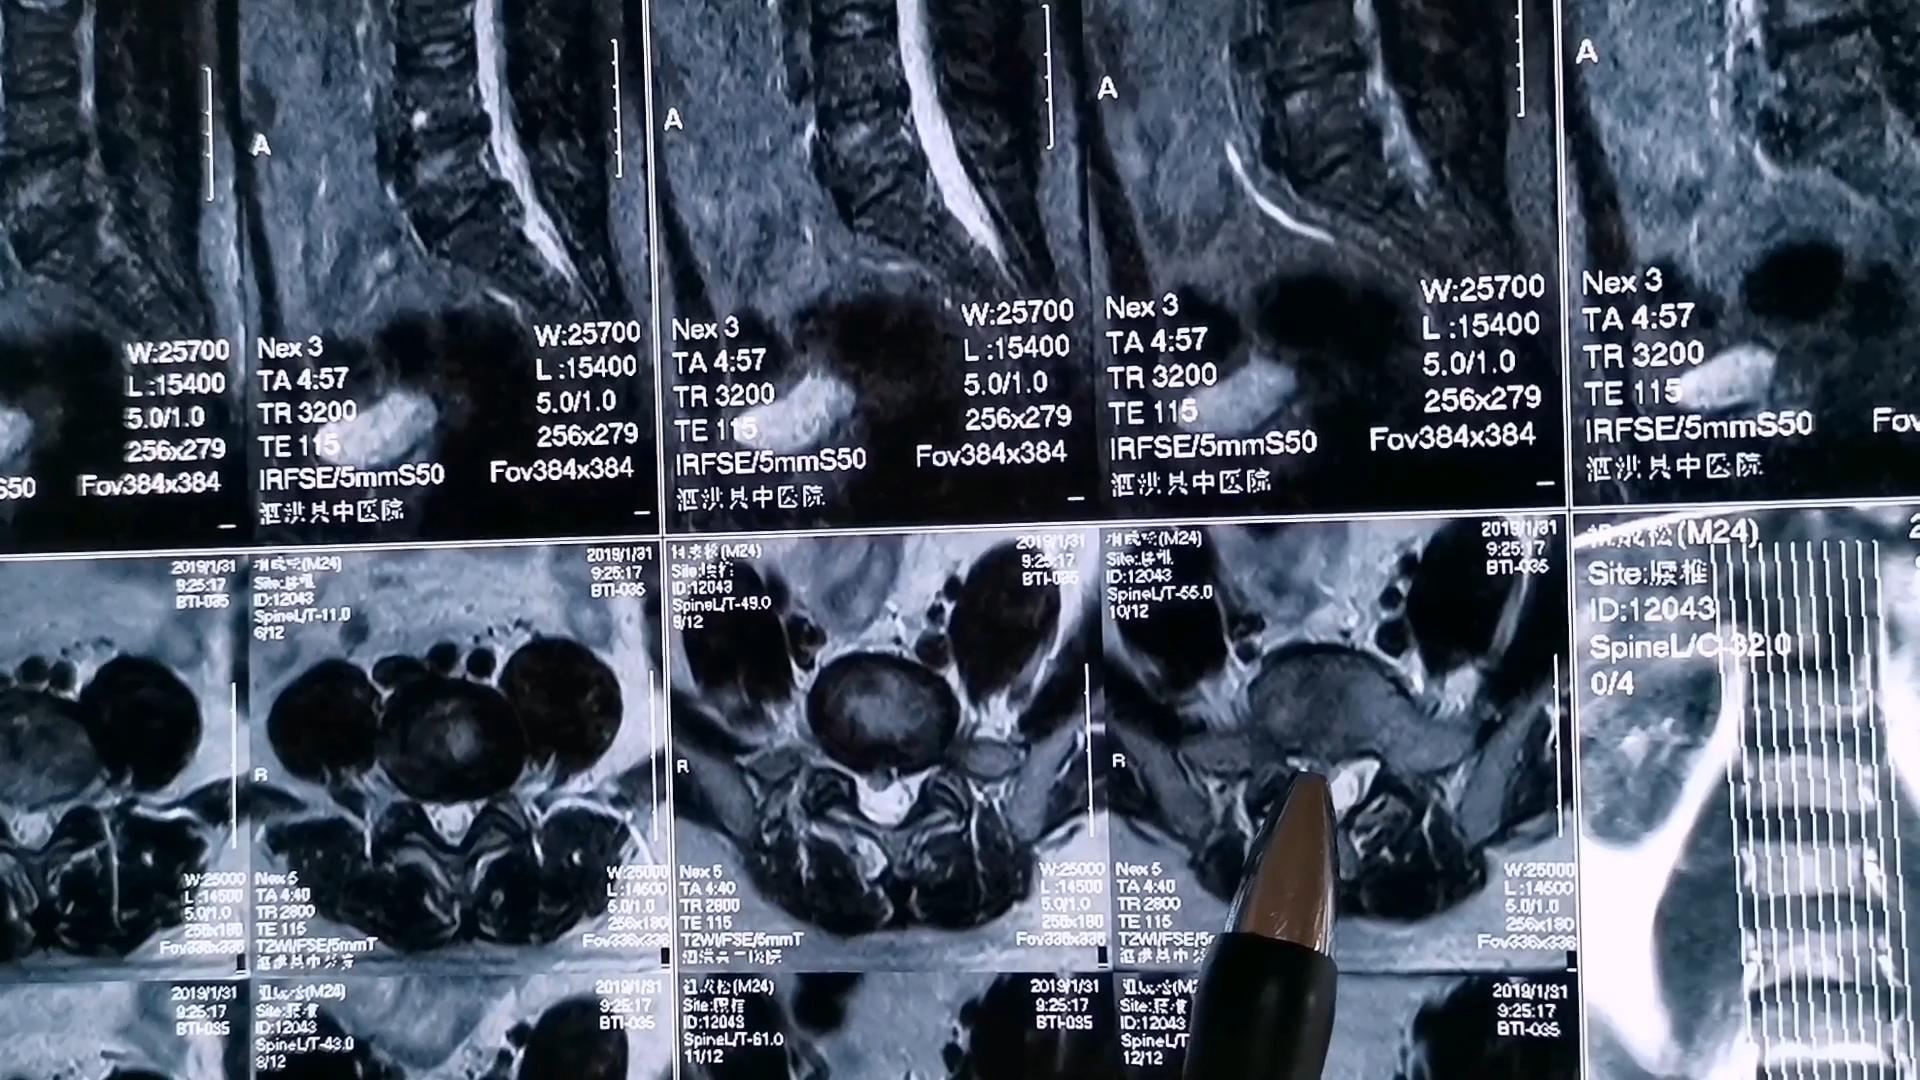

2、体格检查:腰部有无压痛点,压痛点位置在什么地方,在L4/5,还是L5/S1处,或是其他位置。坐骨神经循行处有无压痛。3、直腿抬高试验,以及加强试验是否阳性。4、影像学检查,CT或MR有腰椎间盘突出的征象。